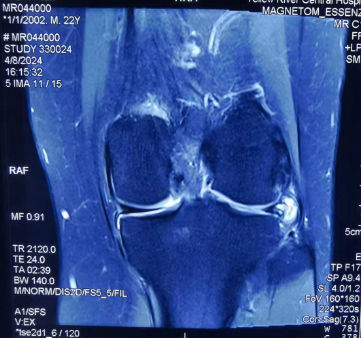

在朋友的介绍下来到郑州大学第五附属医院骨科三病区诊治。接诊的主任医师闫鹏仔细询问患者病史并进行查体,考虑半月板损伤,遂嘱患者进行磁共振检查。MRI检查结果显示,左膝关节外侧半月板撕裂。经过仔细认真的沟通,患者接受了关节镜微创手术治疗。

由于患者年轻,活动量大,且新鲜损伤,主任医师闫鹏为陈某实施了膝关节镜下半月板缝合修复术,手术仅需要做2个5mm小切口,术中直视下证实了患者半月板撕裂。手术非常顺利,最大程度保留了患者的半月板,且切口很小,不影响美观。

▲ 术前左膝MRI